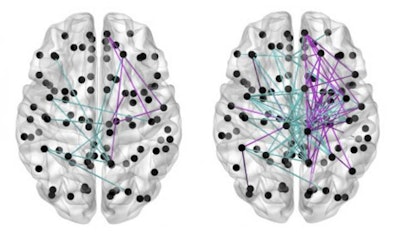

Brain maps based on data from MRI scans show that babies who received more breast milk (left) had fewer gaps in neural connectivity (colored lines) than babies who received less (right). Image courtesy of the Jennifer Brown Research Laboratory at the University of Edinburgh."Mothers of preterm babies should be supported to provide breast milk while their baby is in neonatal care -- if they are able to and if their baby is well enough to receive milk -- because this may give their children the best chance of healthy brain development," Boardman said in a statement from the university.